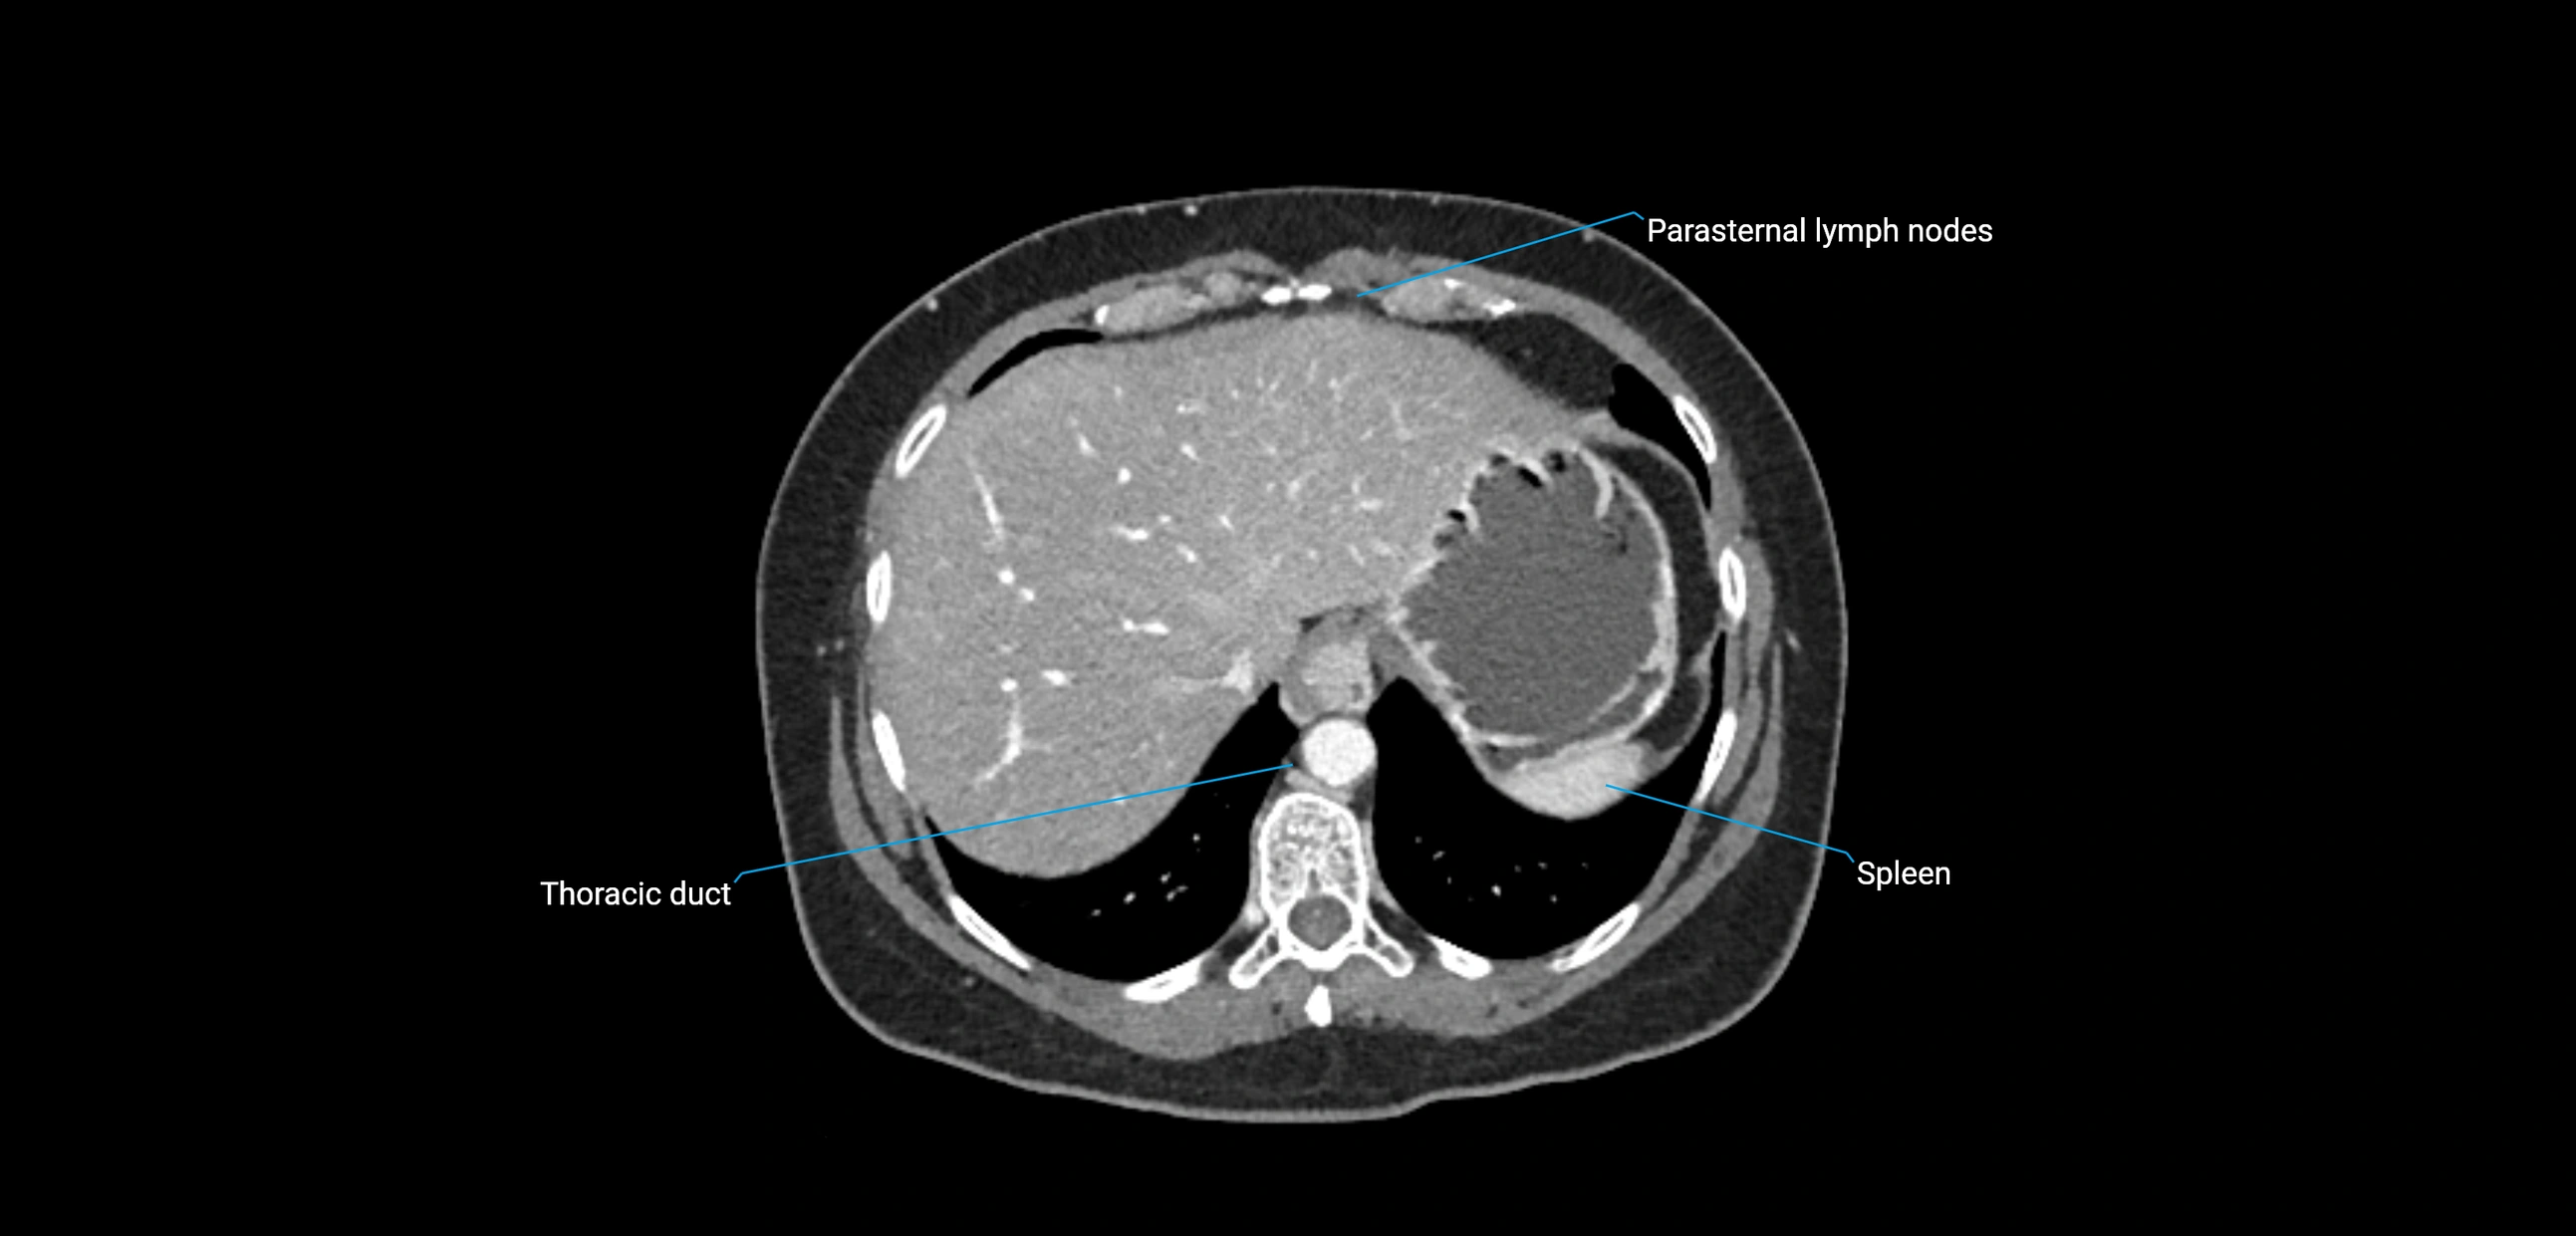

CT Appearance

CT Pre-Contrast:

• Nodes appear as soft-tissue density nodules adjacent to the aorta and IVC

• Calcification may be seen in chronic infections (e.g., tuberculosis)

CT Post-Contrast:

• Normal nodes enhance homogeneously

• Malignant nodes may show heterogeneous enhancement, central necrosis, or conglomerate formation

• Size >1 cm short axis is suspicious, though morphology and distribution are equally important

CT image

image